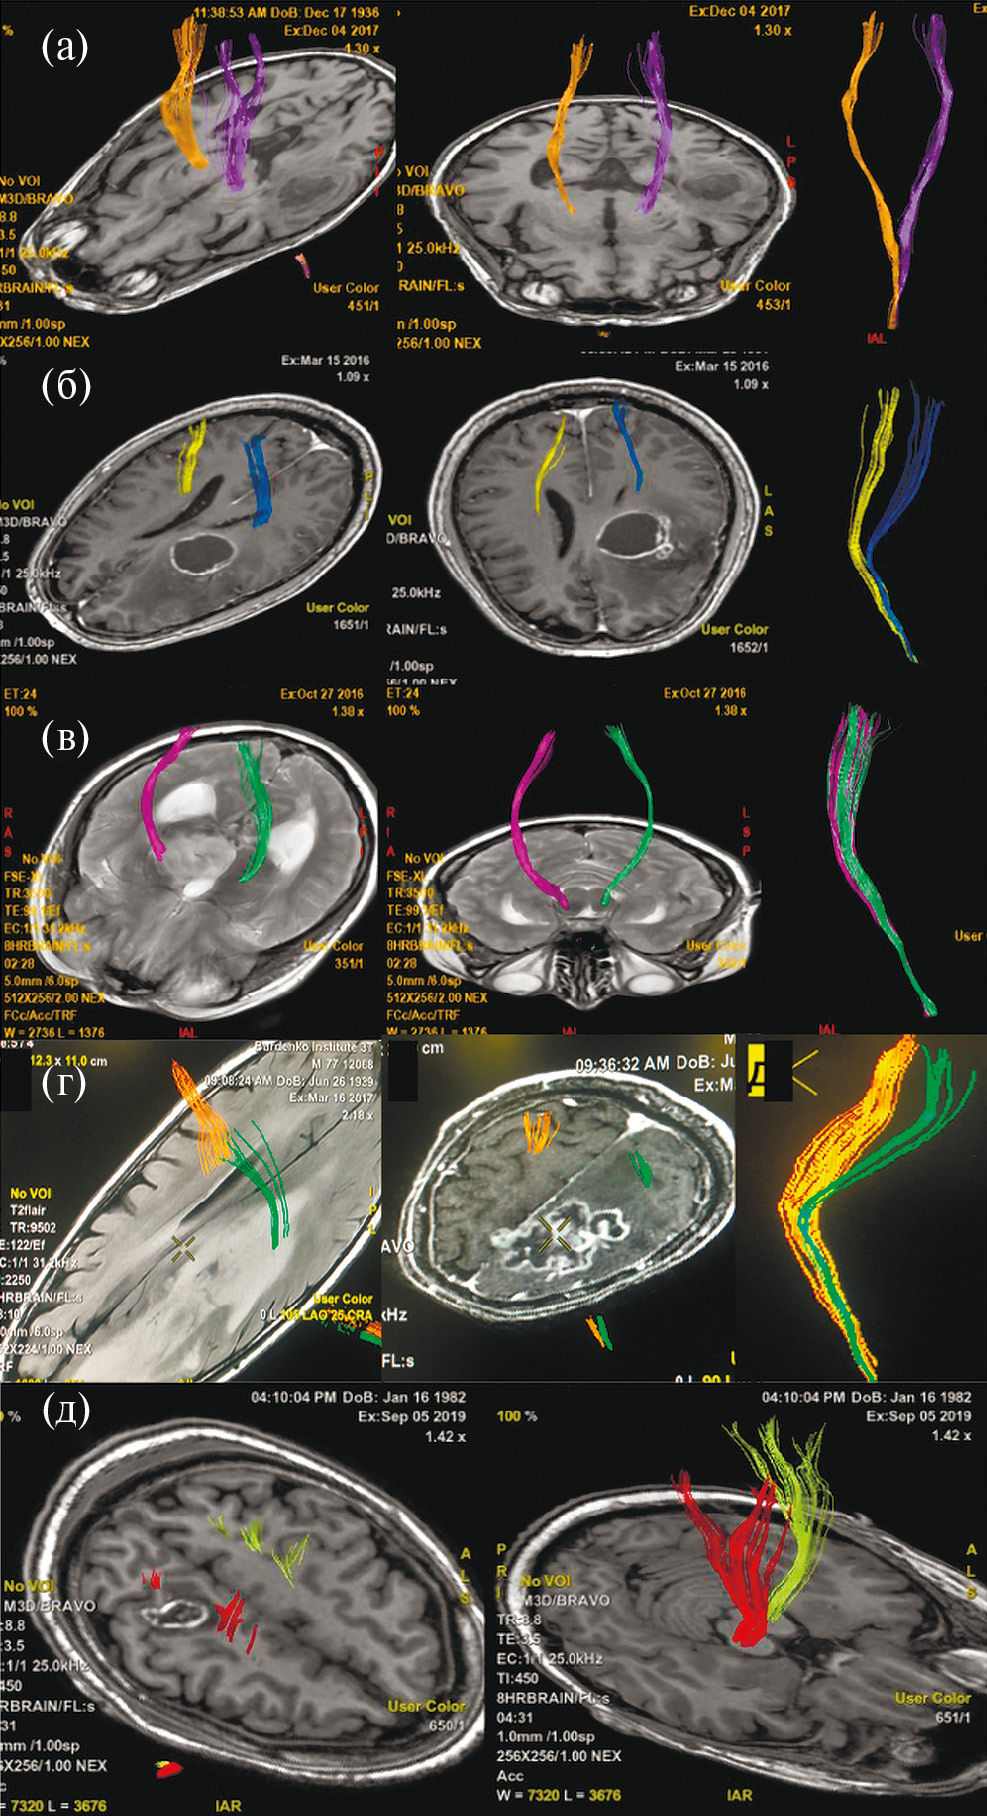

Аласенс (препарат 5-аминолевуленовой кислоты) вводился перорально за 2 ч до разреза ТМО из расчета 20 мг/кг. Из исследования были исключены 12 пациентов, у которых не отмечалось визуальной флуоресценции во время операции. Всем пациентам была проведена оценка мышечной силы до операции, на первые и седьмые сутки после хирургического лечения, выполнена предоперационная МРТ (Т1, Т2, Т2-FLAIR, DWI, T1+C, DTI) с определением расстояния от опухоли до КСТ и типа взаимоотношения между трактом и новообразованием. Было показано, что из 108 пациентов у 21 (19.4%) наблюдался интактный КСТ, у 43 (39.8%) – смещенный, у 34 (31.5%) – смещенный и инфильтрированный, у 8 (7.4%) – инфильтрированный, и только в одном наблюдении опухоль располагалась в структуре тракта, расщепляя его (рис. 1).

Рис. 1. (а) – пример интактного КСТ по данным ДТ-трактографии у пациента с глиобластомой. Тракты симметрично расположены и не отличаются значимо по объему. (б) – пример смещенного КСТ, по данным ДТ-трактографии у пациента с глиобластомой. Тракты не вовлечены в опухоль, однако положение их отличается. (в) – пример инфильрированного КСТ, по данным ДТ-трактографии у пациента с глиомой Grade IV. Несмотря на вовлечение КСТ в опухоль, по данным Т2-FLAIR отмечается правильное, симметричное положение тракта. (г) – пример смещенного и инфильтрированного КСТ, по данным ДТ-трактографии у пациента с глиобластомой. Тракты расположены асимметрично и вовлечены в зону отека-инфильтрации. (д) – пример расщепленного тракта у пациента с анапластической астроцитомой. Опухоль располагается внутри КСТ, расщепляя его волокна.

Fig. 1. Different types of relationship between the corticospinal tract and the tumor according to MR-tractography (intact, displaced, infiltrated, displaced and infiltrated, split).